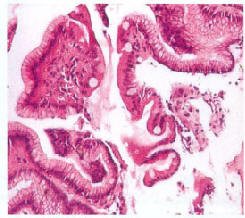

Наиболее характерные гистологические изменения при рефлюкс-гастрите приведены в таблице 2 и на рис. 9-14.

Рис. 10. Кишечная метаплазия. Обширные области кишечной метаплазии с выраженным воспалением (по С. С. Vere et al., 2005 [56])

Рис. 11. Кишечная метаплазия (ограниченные области) (по С. С. Vere et al., 2005 [56])

Рис. 12. Изолированная метаплазия железистого эпителия (по С. С. Vere et al., 2005 [56])

Рис. 13. Изолированная метаплазия железистого эпителия и низкая степень воспаления в lamina propria (по С. С. Vere et al., 2005 [56])

Рис. 14. Воспаление и метаплазия железистого эпителия (по С. С. Vere et al., 2005 [56])

О. Я. Бабак подтверждает, что для рефлюкс-гастрита типичны фовеолярная гиперплазия и отек слизистой, а также отмечает пролиферацию гладкомышечных клеток в собственные пластинки на фоне умеренного воспаления. Фовеолярную гиперплазию определяют как экспансию слизистых клеток. При рефлюкс-гастрите она охватывает исключительно поверхностный эпителий и этим отличается от гастрита типа В (хеликобактерного), для которого характерна гиперплазия не только поверхностного, а и ямочного эпителия слизистой оболочки желудка. Эпителий становится резко уплощенным, базофильным, насыщенным РНК и почти не содержащим слизи. В клетках эпителия отмечаются грубая вакуолизация цитоплазмы, пикноз ядер, некробиоз и некроз, который считается началом образования эрозий. Со временем нарастают атрофические изменения, сопровождающиеся прогрессированием пролиферативных процессов и развитием дисплазии различной степени выраженности, что увеличивает риск малигнизации [2, 4, 36].